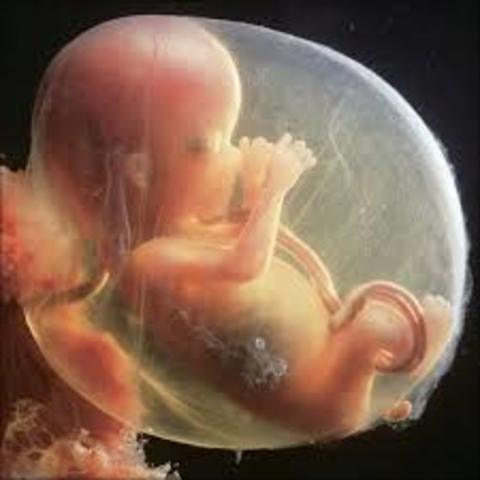

• semana 8 de embarazo

semana 8 de embarazo

primeros rasgos. La placenta le alimenta

Durante la semana 8 de embarazo el feto medirá entre 1,4 y 1,8 centímetros. Ya tiene párpados, labio superior y nariz y orejas se están empezando a formar. El cuerpo se está alargando, pueden reconocerse lo que serán brazos y piernas, y es posible ver el esqueleto a través de su piel, que es translúcida. El esqueleto está formado por un cartílago suave todavía, no son huesos.